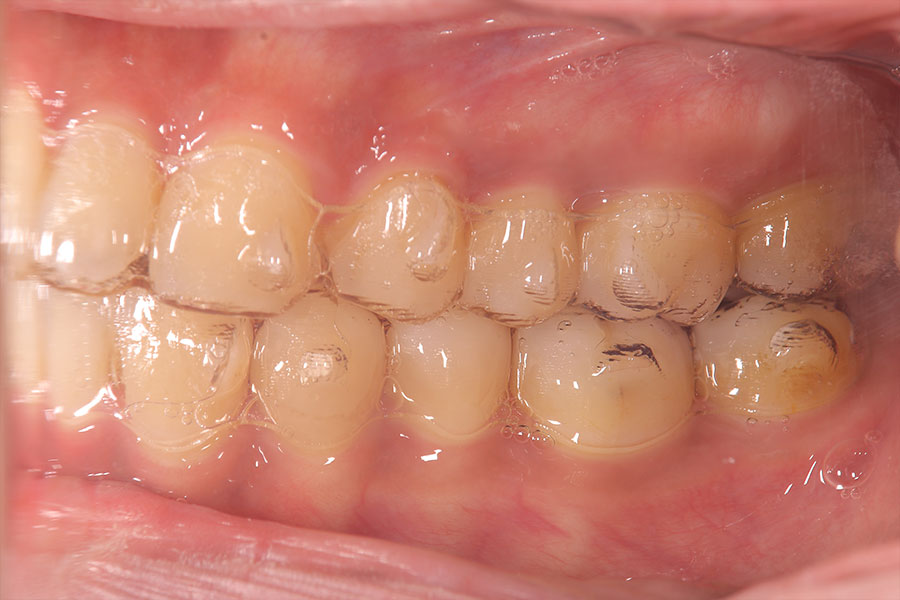

Before -側面-

After -側面-

| 施術内容 | ワイヤー矯正から、目立ちにくくメタルフリーなインビザラインへ変更しました。 金属アレルギーの不安が軽くなり、取り外しできることで清掃性も向上。見た目も自然で、治療中のストレスが少ない矯正方法です。 |

|---|---|

| 治療期間 | 2年間 |

| 費用 | インビザラインフル 767,800円 リテーナー 30,000円 |

| リスク・副作用 | 治療にともない、歯の破折や歯質の削合、場合によっては抜歯が必要となることがあります。また、金属や補綴物を除去する際に、完全に除去できない場合もあります。 |